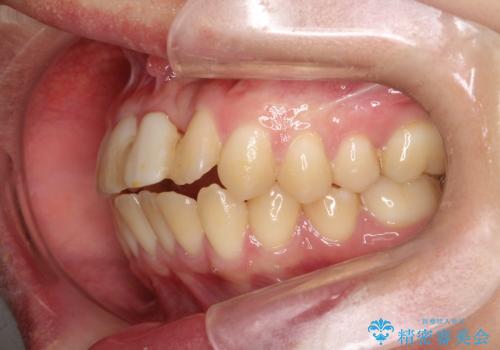

前歯の開咬とシザーズバイトを改善|インビザライン矯正

- 治療計画

前歯が噛まないため咀嚼が困難で、シザーズバイトにより噛み合わせに不調を感じていました。インビザラインを用いて、透明なマウスピースによる目立ちにくい矯正治療を実施。奥歯のシザーズバイトを改善した後、前歯の歯列を緻密に調整し、噛み合わせを整えました。定期的なマウスピース交換を通じて徐々に歯列が改善され、治療終了後には前歯が正常に咬合するようになり、噛み合わせの機能性と審美性が共に向上しました。